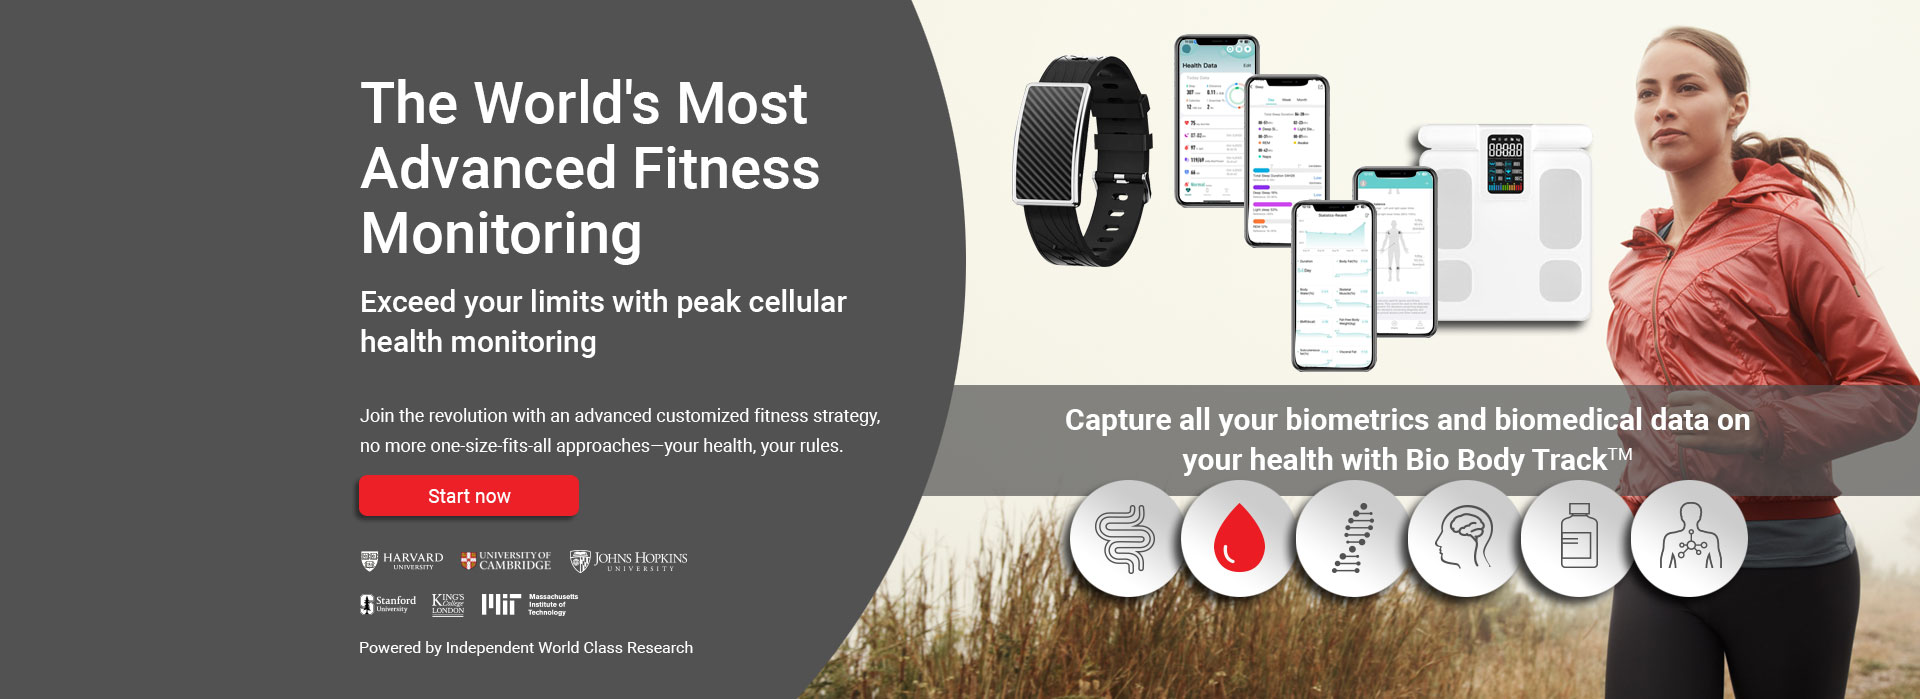

Learn about your current condition and activate your Bio Body Track devices and biomedical monitoring.

Develop and start a plan based on your Biomedical condition and monitor everything with our devices and services.

Capture your biometrics and biomedical data and make the changes to reach your goals and obtain optimum health.

We place you into our unique Biomedical Fitness eco system where your healthcare data, tests, and how you feel inside, and outside are constantly monitored.

We place our clients into biomedical fitness healthcare ecosystem, ensuring that your path to success is well-coordinated and managed by our team.

| Bio-Medical Smart Watch or Health band |  |

| Real-time remote glucose monitoring - before, during, and after workouts |  |

| Specialized Digital Biomedical Body tracking scales - bone, muscle, water & fat monitoring |  |

| Sleep monitoring – duration, type and quality |  |

| Stress level monitoring |  |

| Real-time oxygen levels (spo2) pre-, during, and post-workout |  |